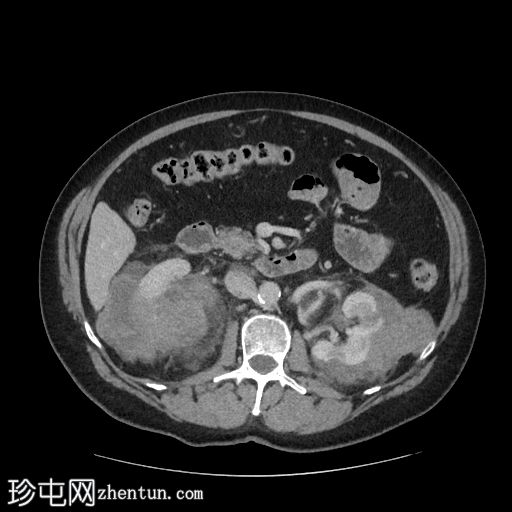

矢状位增强扫描(门静脉期)

右肾可见不规则分叶状低密度浸润性病变,超出肾包膜,并与右肝下叶相邻。

左肾可见弥漫性浸润性病变,以上极为中心。左肾浸润性病变与胰尾相邻,胰尾可能受累,表现为胰腺后缘不规则、脂肪间隙消失。此外,浸润性病变与左侧肾上腺外侧肢相邻。

脾脏下极可见一密度不明、呈分叶状/浸润性改变的肿块。

本例为肾淋巴瘤,具体为弥漫性大B细胞淋巴瘤(DLBCL)。

鉴于其浸润性病变,高度怀疑为淋巴瘤。原发性肾脏恶性肿瘤(例如肾细胞癌、肾嗜酸细胞瘤)的可能性较小。肾脏肿块活检证实为肾脏DLBCL。